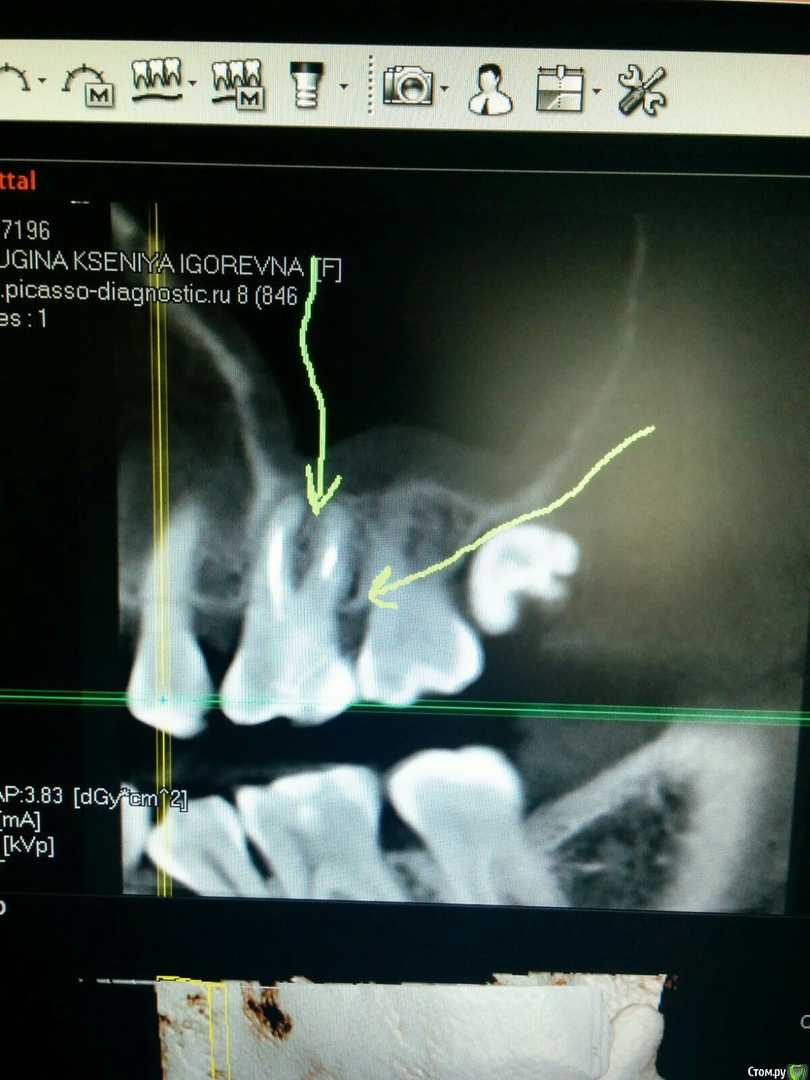

Ксения33 Опубликовано 30 сентября, 2020 Поделиться Опубликовано 30 сентября, 2020 (изменено) Уважаемые доктора, подскажите, пожалуйста, за какой срок восстанавливаются ткани периодонта? Мне перелечивали сложный зуб с хроническим периодонтитом. На снимках были значительные изменения. Как вы считаете, когда целесообразно сделать повторное КТ для оценки состояния периодонта в области этого зуба? Прикладываю снимки до перелечивания каналов. Изменено 30 сентября, 2020 пользователем Ксения33 Ссылка на комментарий